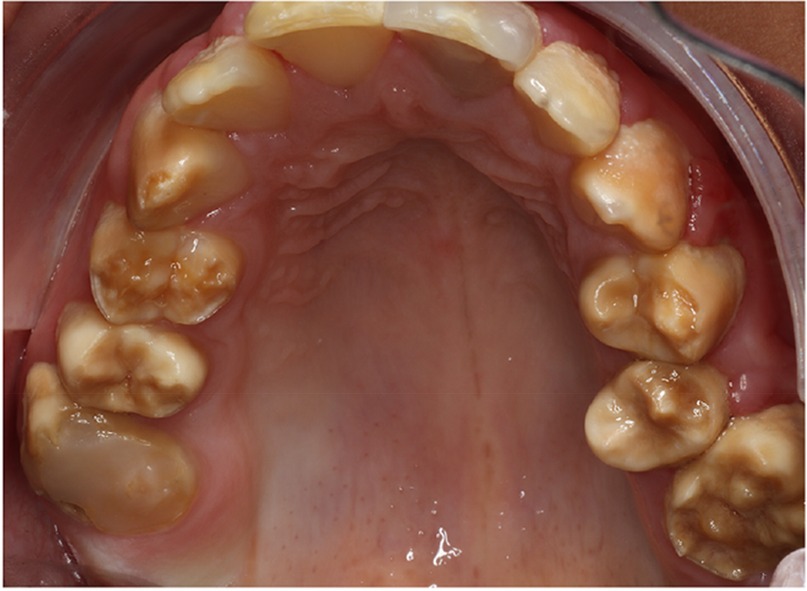

A cluster of Māori children in Northland (New Zealand) are known to have a moderate-to-severe hypo-maturation form of AI known as “Polynesian Amelogenesis Imperfecta” (or Poly AI) which is found in people of Polynesian ancestry, including New Zealand Māori (6–9). Poly AI is characterised by a bilaterally symmetrical hypo-mineralised dentition, mottled or uniformly yellow to brown in colour, with an anterior to posterior gradient in severity. Figures 1, 2 show typical Poly AI cases. Its prevalence in the wider New Zealand Māori population and other Polynesian populations is unknown. Its occurrence in the primary dentition is also poorly understood, possibly due to limited phenotypic expression in that dentition. The chalky nature of the teeth predisposes to post-eruptive breakdown and hypersensitivity with a high associated treatment burden and poorer oral health. While some of the anterior dentition may be only mildly affected, this is not always the case, and the canines and premolars (which are within the smile line) can have poor aesthetics.

Figure 1. A typical Poly AI patient with maxillary hypomineralised dentition exhibiting mottled yellow and brown discolouration.